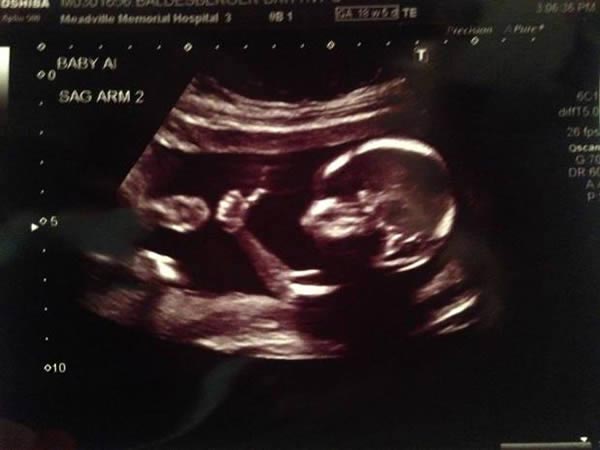

அல்ட்ராசவுண்ட் ஸ்கேன் செய்வது குழந்தையை பாதிக்குமா?

அடிக்கடி அல்ட்ராசவுண்ட் ஸ்கேன் செய்வது சரியானதா என்பது பற்றி கொடுக்கப்பட்டுள்ளது.

அல்ட்ராசவுண்ட் ஸ்கேன் பல வருடங்களாக பயன்படுத்தப்பட்டு வருகிறது. ஆனால் இதனால் ஆபத்தான விளைவுகள் ஏற்படுவதற்கான எந்த ஒரு ஆதரமும் இல்லை.

- உங்களுக்கு இரட்டை குழந்தை அல்லது அதற்கு மேற்பட்ட குழந்தைகளாக இருக்கலாம்.